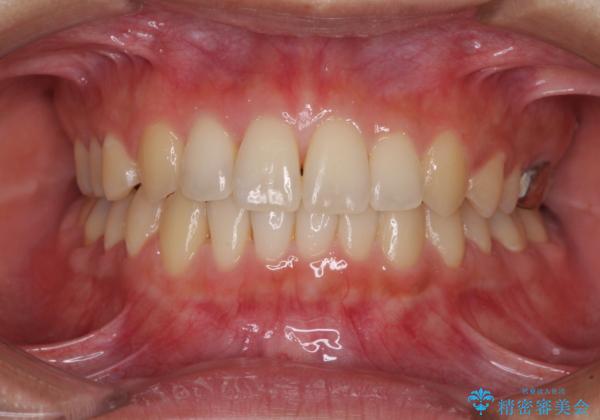

海外勤務中のインビザラインによる矯正治療

- 前歯のクロスバイトを気にして来院され患者様です。

定期的に日本には帰国するものの、日ごろは海外でお仕事をされているとのことで、インビザラインによる治療を希望されました。

トラブルが起こった時に対応ができない、来院を帰国のタイミングに合わせなければならないため治療が長期化するなど困難はありますが、ワイヤー矯正と比べると治療を進めやすいといったメリットがあるので、インビザラインにて矯正治療を行うこととしました。

治療期間が世界的な感染症の流行時期と重なったため、海外と日本での往来が困難となり、治療継続が懸念されました。

それでも、しっかりとマウスピースを装着してくださったので、大きなトラブルもなく治療を終えることができました。